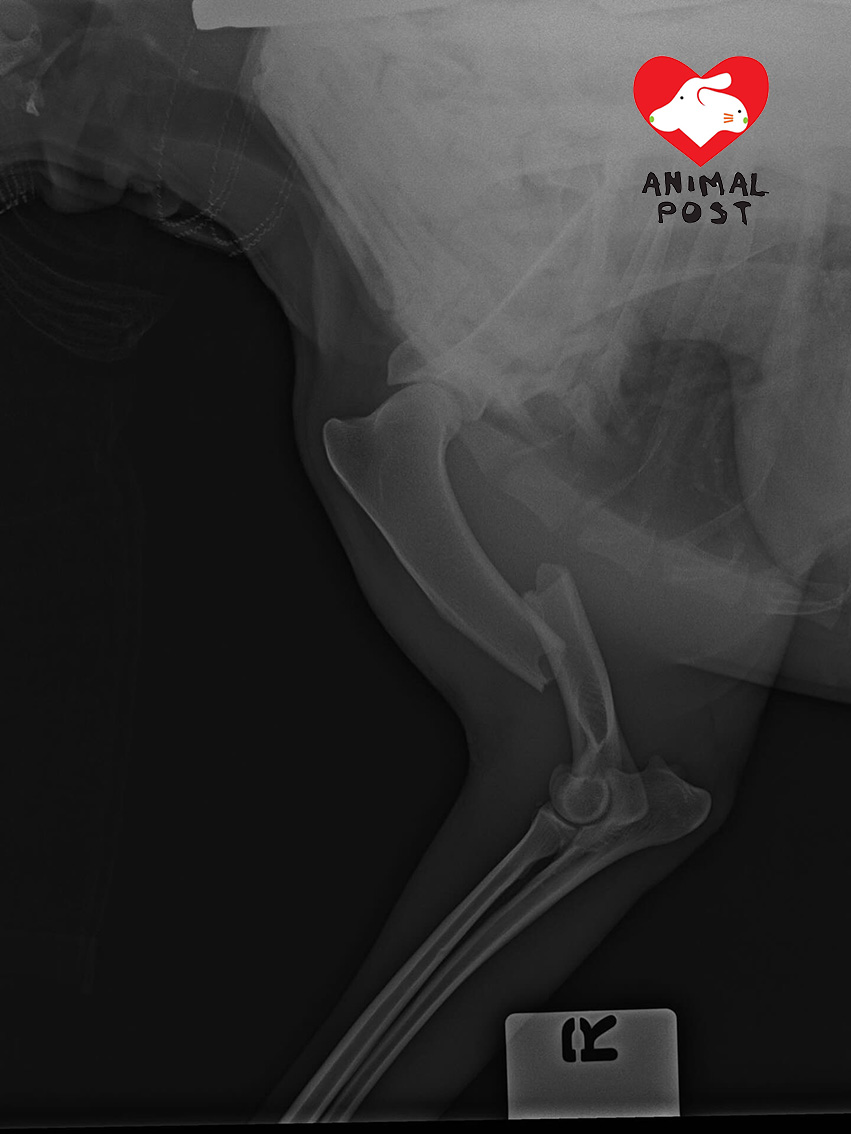

經過檢查後,發現朱古力傷勢極嚴重,右前腳的骨頭被BB彈打至完全骨折,甚至右前腳後方出現一小點凸起有紅印,很可能是BB彈由前方進入前腳,繼而打穿骨頭導致骨折,更幾乎直接貫穿。獸醫明言朱古力必須盡快接受手術,否則可能要截肢,甚至有喪命風險。而高飛雖然也有受傷,幸好並無大礙。她又表示,在事發現場附近發現4粒新的黃色BB彈,並指氣槍威力這麼嚴重,連愛協獸醫都指未見過塑膠彈能夠打穿狗狗骨頭,她懷疑是涉及非法改裝氣槍。